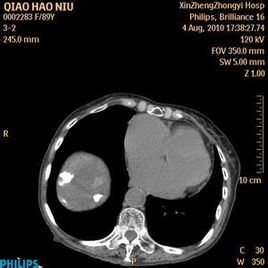

多數情況下,肝臟的鈣化斑只是人體肝細胞壞死之後產生的一些特殊的變異,人體每天都在進行新陳代謝,一些細胞壞死是正常現象,壞死之後,因為自身循環不暢,從而在肝膽中沉著下來,形成鈣化斑,在b超下顯示出很像是結石的亮點。

一般情況下,對身體並沒有太大的影響。這種斑點在b超檢查中只有0.5cm左右。鈣化斑如同皮膚上長的痣,只是一些壞死細胞的沉著,大多數是良性的,而且病人本身大多數都沒有什麼症狀,一般情況下不用處理。

但在某些情況下,肝炎、脂肪肝、糖尿病、死亡蟲卵等都可以引起肝細胞的改變,因此,也要排除這些疾病引起病變的可能。

形成肝內鈣化灶的病變很多,它主要包括:

①肝內膽管結石,是最常見的因素;

②肝內慢性炎症或創傷;

③寄生蟲感染;

④肝臟良惡性腫瘤和肝內轉移瘤鈣化;

⑤先天發育形成,子宮內的胎兒有肝內鈣化灶形成,常合併先天畸形,發現率為0.057%。